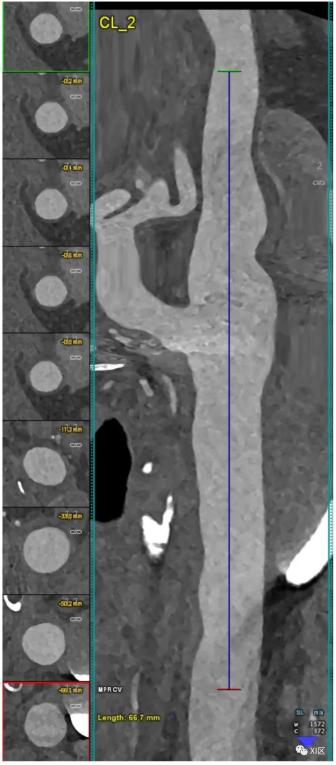

颈动脉分叉的PCCT血管造影:轻度非钙化动脉粥样硬化。PCCT血管造影显示了超高清(源数据集;矩阵1024×1024;层厚/增量0.2/0.1mm;体素100 μm;卷积核Bv60;辐射剂量与使用第三代双源CT进行的同等颈动脉血管造影相当)颈动脉分叉的纵向CPR成像,动脉壁有轻度弥漫性非钙化动脉粥样硬化。

颈动脉分叉的PCCT血管造影:中度混合性和钙化性动脉粥样硬化。PCCT血管造影显示了2个超高清(源数据集;矩阵1024×1024;层厚/增量0.2/0.1mm;体素100 μm;卷积核Bv60;辐射剂量与使用第三代双源CT进行颈动脉血管造影的同等剂量相当)颈动脉分叉处有严重钙化的动脉粥样硬化斑块((A);纵向和轴向视图)和中度/中度混合/钙化斑块((B);纵向和轴向视图)。值得注意的是,(A)中斑块的大块钙化完全分布在动脉壁内,不影响最终管腔狭窄的观察和量化。